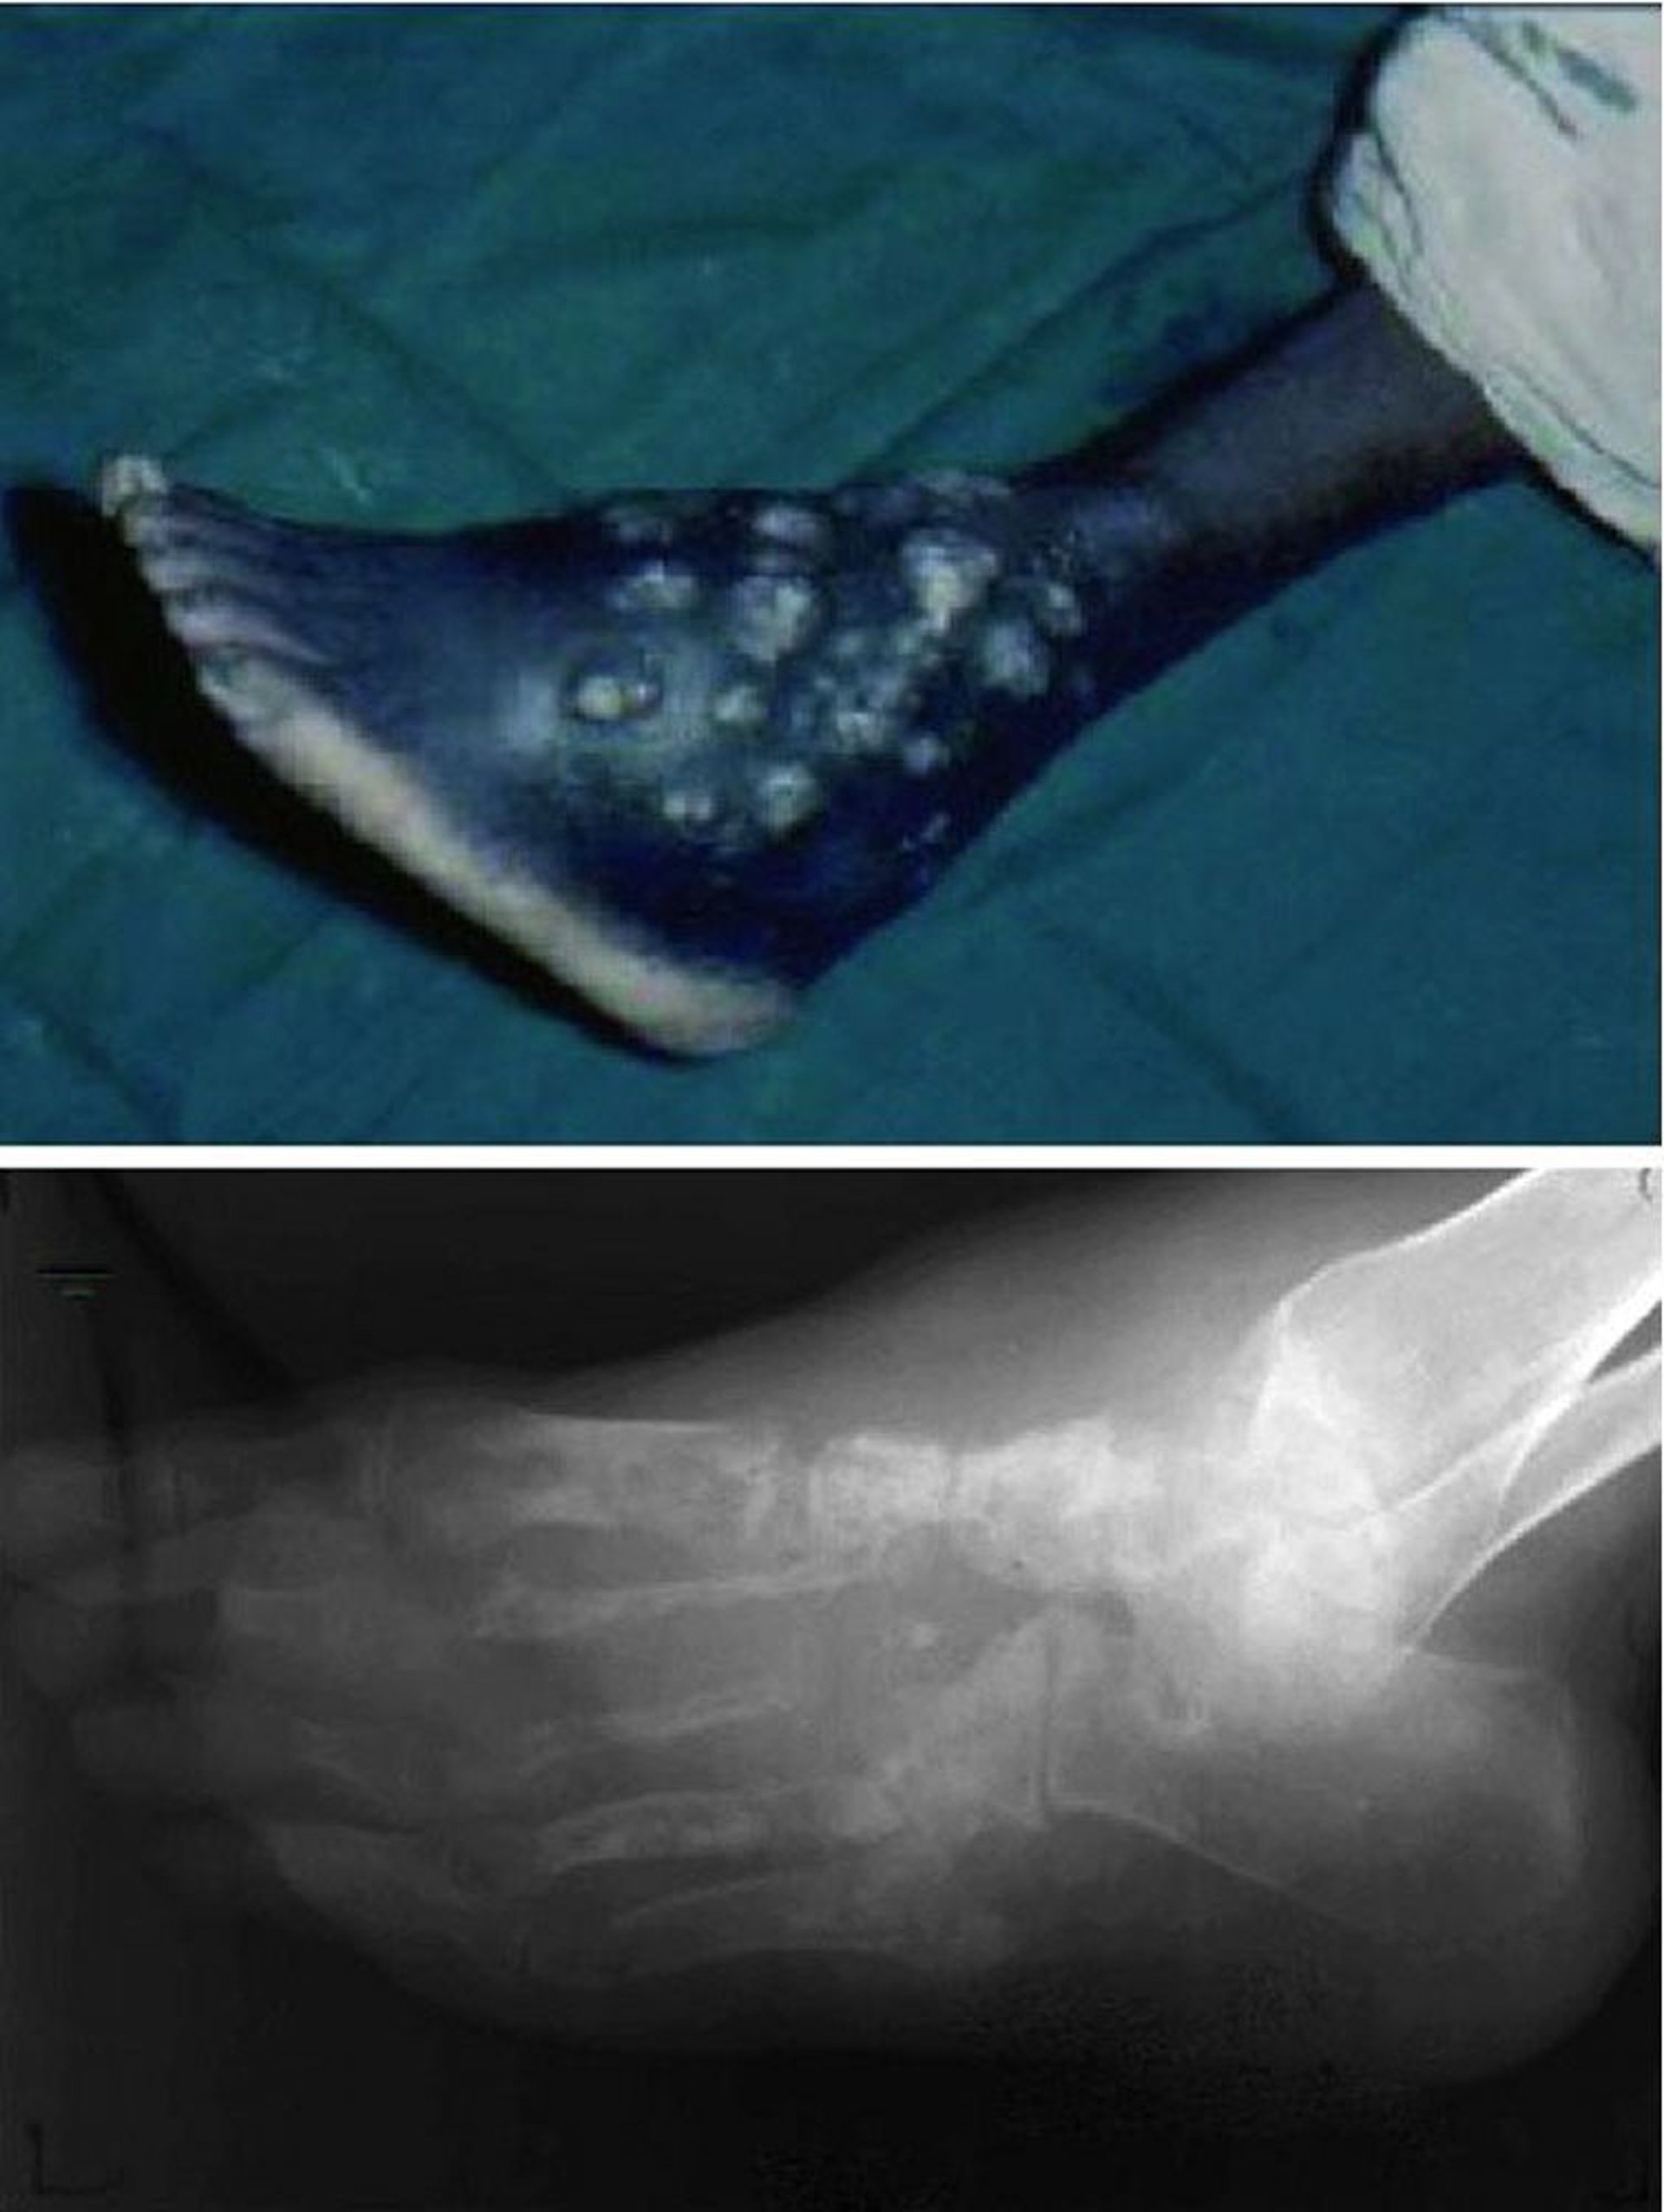

Myzetom (Madura-Fuß)

Dieses Foto zeigt chronische, nicht heilende Wunden mit wiederkehrenden Episoden von Drainage und Ulzeration (oben) und fortschreitender Zerstörung der gesamten knöchernen Architektur des Fußes (unten).